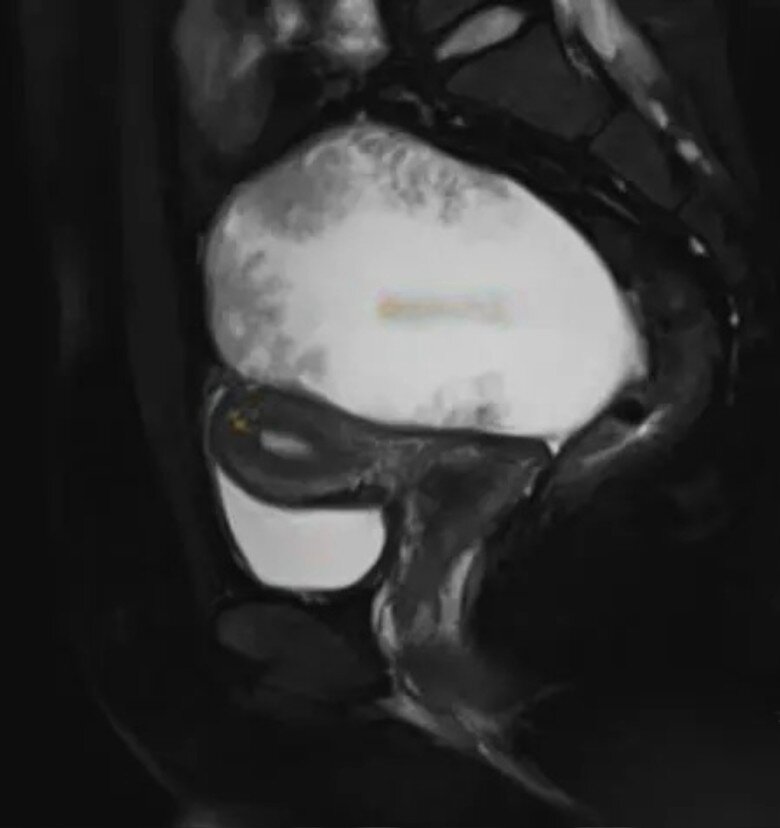

Tại phòng khám phụ khoa, bác sĩ tiến hành siêu âm lại. Chỉ vài phút sau, gương mặt ông biến sắc: hình ảnh cho thấy buồng trứng phải xuất hiện một khối u kích thước hơn 10 cm, cấu trúc hỗn hợp giữa dịch và mô đặc, kèm theo tín hiệu mạch máu tăng mạnh. Điều này khiến bác sĩ lập tức yêu cầu bệnh nhân làm thêm xét nghiệm máu và chụp MRI vùng chậu để loại trừ khả năng bệnh lý nghiêm trọng.

Kết quả trả về chỉ vài giờ sau đó khiến cả ê kíp y tế lẫn bệnh nhân “đứng hình”: chỉ số CA125 - dấu ấn khối u liên quan ung thư buồng trứng của Tiểu Tây quá cao đến mức máy xét nghiệm không đo nổi. Kỹ thuật viên buộc phải pha loãng mẫu máu nhiều lần để có thể đọc được con số cuối cùng: hơn 20.000 U/ml, trong khi giá trị bình thường là dưới 35 U/ml.

Kết quả siêu âm của bệnh nhân khiến bác sĩ bất ngờ.